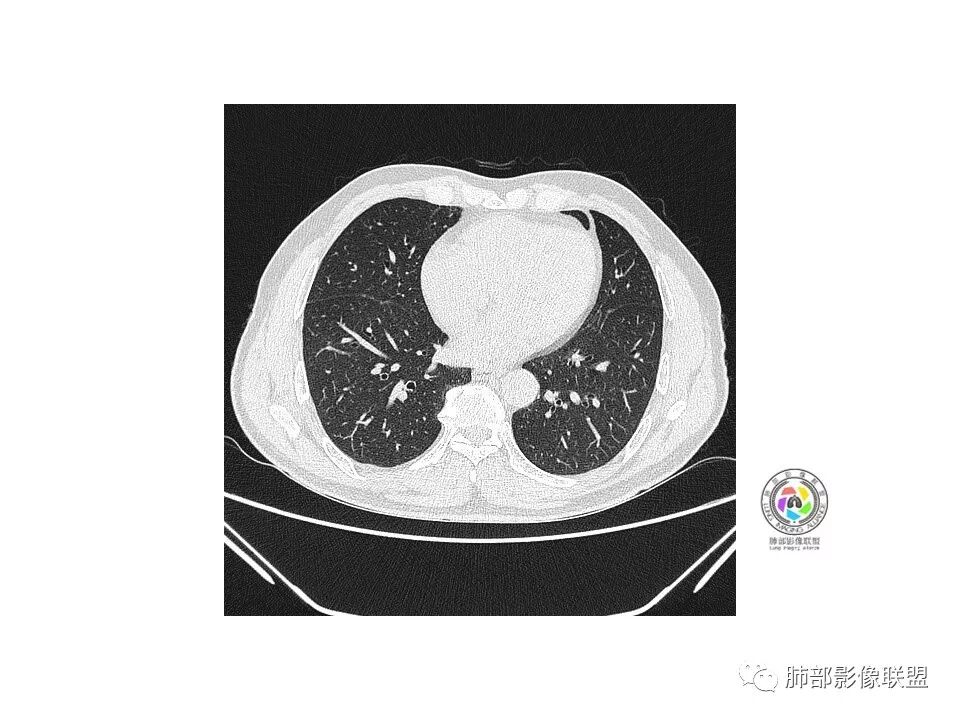

彭君:

右肺下叶前基底段混合磨玻璃密度结节 边缘见月牙铲 部分边缘清 部分似清非清 远端见磨玻璃片影,炎性和粘液腺癌鉴别 先抗炎复查

流心明智:

老年男性,咳嗽、咳痰3天。胸部CT:右肺下叶前基底段mGGN,边缘清楚,内可见不规则实性成分,病灶可见空泡、毛刺、胸膜牵拉、血管集束征象。考虑MIA可能大,抗炎2W后复查。

老年男性,右下肺前基底段混合GGN,边缘清晰,月牙铲,叶间胸膜牵拉,有轻度收缩力。结合病史抗炎2-3周后复查,消失考虑炎症,变化不大为腺癌。本例总体支持腺癌

孙冰伟:

老年男性,咳嗽3天,右肺下叶前基底段混合磨玻璃结节,形态不规整,相邻胸膜凹陷,可见血管影,考虑腺癌可能性大,不除外炎症可能,建议抗炎1~2周,1个月复查胸部CT。

红日东升:

右肺下叶mGGN,内部结构紊乱,可见小点状高密度影,边缘清晰,小叶间隔阻挡,轻度收缩力,考虑MIA,常规飞一会20天复查。

右肺下叶磨玻璃影,边界似清非清(考虑部分为血管断面围绕),周边见条索灶,胸膜牵拉弱。我把炎症放前面,建议抗炎治疗后复查除外恶性。

小赵:

老年男性,右肺下叶前基底段GGN,界清,内部血管结构杂乱,叶间胸膜牵拉。考虑恶性,早期腺癌可能,建议抗炎治疗后复查对比。

张延军:

右肺下叶前基底段见一磨玻璃结节影,呈分叶状,边缘部分模糊,与胸膜间有长条索粘连,内有增粗的血管影,后者边缘毛糙,考虑微浸润性腺癌,建议抗炎治疗后复查

心灵鸡汤:

老年男性,右肺下叶前基底段斜裂旁可见单个混合型磨玻璃结节mGGN,边缘清,内部结构紊乱,进入的血管增粗,支气管关系不好判断,斜裂侧可见牵拉,常规考虑微侵腺癌MIA,建议先抗炎后复查及手术干预。

傅昌瑜:

老年男性,咳嗽咳痰3天。MGGN,边缘见月牙铲、胸膜牵拉,血管移动联通?冠状位隐约可见支气管穿行,考虑MIA,重建冠位可见结节比较靠近叶裂,可积极手术处理。

曹志勇:

老年男性,右S8混合磨玻璃结节,边缘尚清晰,局部凹陷,叶间胸膜牵拉,考虑MIA可能大,建议抗炎治疗10天,6-8周后复查